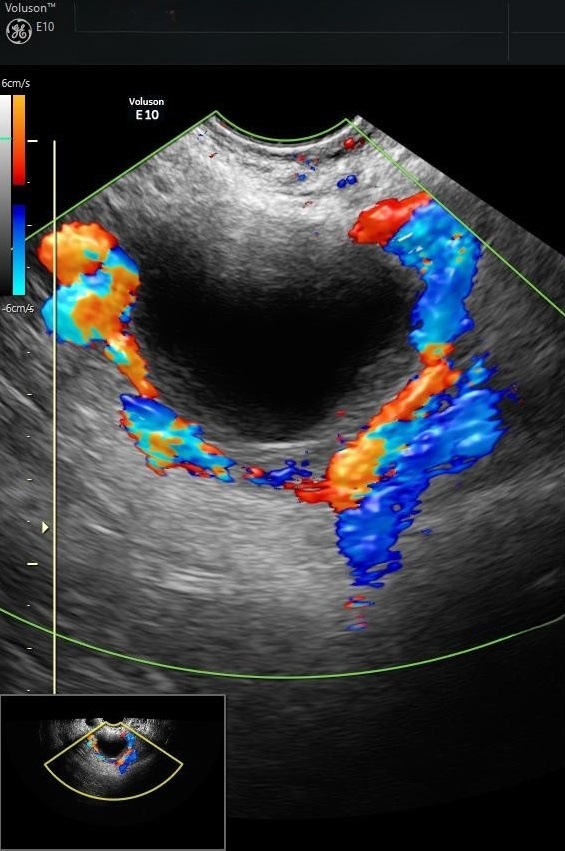

Ca tháo xoắn diễn ra khoảng 30 phút, trong đó thời gian thực hiện thủ thuật chưa đầy 10 phút. Hai ngày sau mổ, hình ảnh siêu âm cho thấy buồng trứng sau khi tháo xoắn đã có máu nuôi trở lại. Bệnh nhân được chỉ định xuất viện sau 2 ngày tiếp theo.

Tái khám một tuần sau đó, kết quả cho thấy mạch máu phục hồi tốt, buồng trứng gần như trở lại bình thường và thai nhi phát triển khỏe mạnh. Gia đình bệnh nhân vui mừng nhờ quyết định đầy quyết đoán của bác sĩ.